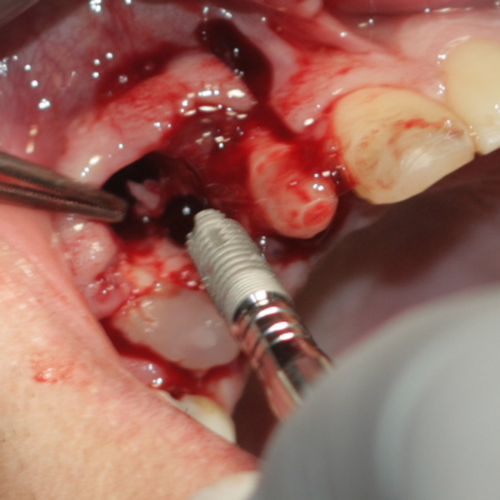

Пациент на възраст 17 години след прекарано ПТП фрактурира зъб 14; зъб 13 е интрудиран дълбоко в костта на горна челюст. Зъб 14 е изграден с композитен щифт; зъб 13 е силно подвижен поради фрактурата на част от алвеоларния гребен вестибуларно и подлежи на екстракция. Травмиращият агент е засегнал зъба във вертикална посока и вероятно с голяма сила - в противен случай не би се получила фрактура на алвеоларния гребен. Случаят представлява казуистична рядкост - обикновено при травми в лицево - челюстната област се стига до фрактуриране или експулсиране на зъби.

Поставяне на имплантат Neobiotech след екстракция и калиброване на алвеолата на зъб 13. След отпрепариране на ламбото се откри подвижен костен фрагмент, който не бе свързан с периост и поради това се отстрани от оперативното поле. Вижда се голям дефект в алвеоларния гребен, който ще бъде запълнен с натрошена кост от фрактурирания фрагмент и костозаместител, за да може да се възстанови нормалния обем и конфигурация на алволарния израстък.

Имплантатът вече е поставен, а дефектът на алвеоларния гребен е запълнен с костозамествасщто вещество Casios. Това ще позволи да се възстанови обемът на липсващата кост, да протече правилно процесът на остеоинтеграция на имплантата и ще подобри прогнозата от лечението. Автогенната кост на пациента беше раздробена с помощта на костна мелница (YDM - Япония - www.ydm.co.jp) и получените костни отпилки баха размесени със синтетичния костозаместващ материал. Според повечето автори това е оптимален вариант при липса на достатъчно автогенна кост - не се налага допълнителн оперативна намеса с цел вземане на допълнителна кост от друг донорен участък. Същевременно автогенната кост бързо се реваскуларизира от организма и се образува допълнителен костен обем.

Екзактно поставени шевове. Следва период на остеоинтеграция на поставения имплантат и протезиране с корона.